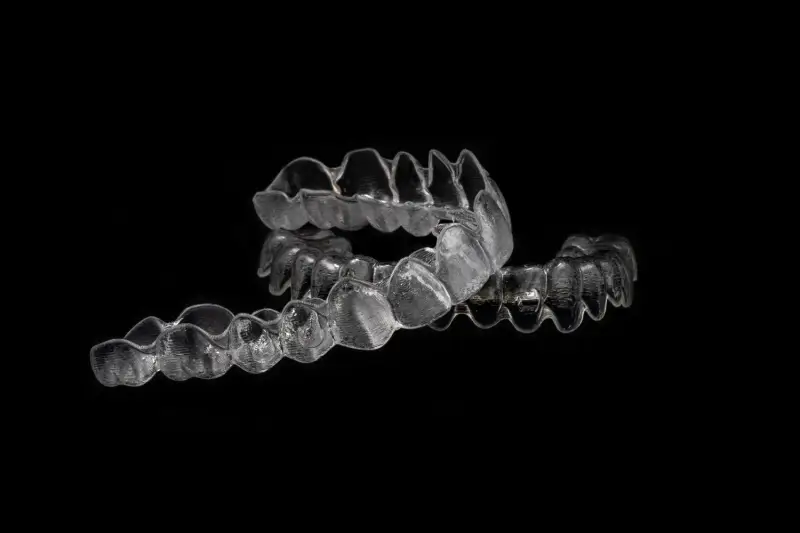

Wiele kobiet zastanawia się, jakie zabiegi stomatologiczne można wykonać w czasie ciąży bez obaw o zdrowie swoje i dziecka. Ogólnie rzecz biorąc, większość rutynowych procedur stomatologicznych jest bezpieczna, jednak zawsze warto skonsultować się z dentystą przed podjęciem decyzji o leczeniu. Profilaktyka jest kluczowa, dlatego regularne czyszczenie zębów oraz kontrole stanu zdrowia jamy ustnej powinny być priorytetem. W przypadku wystąpienia bólu zęba lub innych problemów zdrowotnych nie należy zwlekać z wizytą u dentysty. Leczenie kanałowe może być przeprowadzone w czasie ciąży, ale najlepiej jest to robić w drugim trymestrze. Ekstrakcje zębów również mogą być konieczne, a ich wykonanie powinno odbywać się pod odpowiednim znieczuleniem. Warto jednak unikać niektórych zabiegów estetycznych, takich jak wybielanie zębów czy zakładanie implantów, ponieważ mogą one wiązać się z ryzykiem dla rozwijającego się płodu.